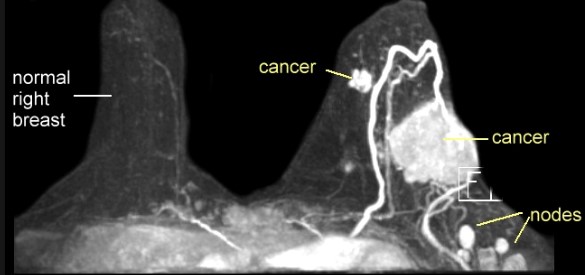

MRI payudara - Benjolan kanker meningkat dengan baik pada gambar MRI